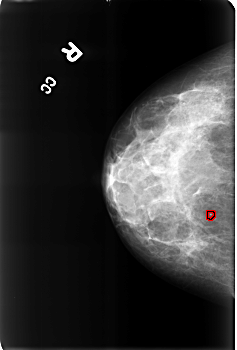

B_3169_1.RIGHT_CC

RIGHT_CC LINES 4544 PIXELS_PER_LINE 3072 BITS_PER_PIXEL 12 RESOLUTION 50 OVERLAY

FILE: B_3169_1.RIGHT_CC.OVERLAY

TOTAL_ABNORMALITIES 1

ABNORMALITY 1

LESION_TYPE CALCIFICATION TYPE LUCENT_CENTERED DISTRIBUTION N/A

ASSESSMENT 2

SUBTLETY 3

PATHOLOGY BENIGN

TOTAL_OUTLINES 1

BOUNDARY